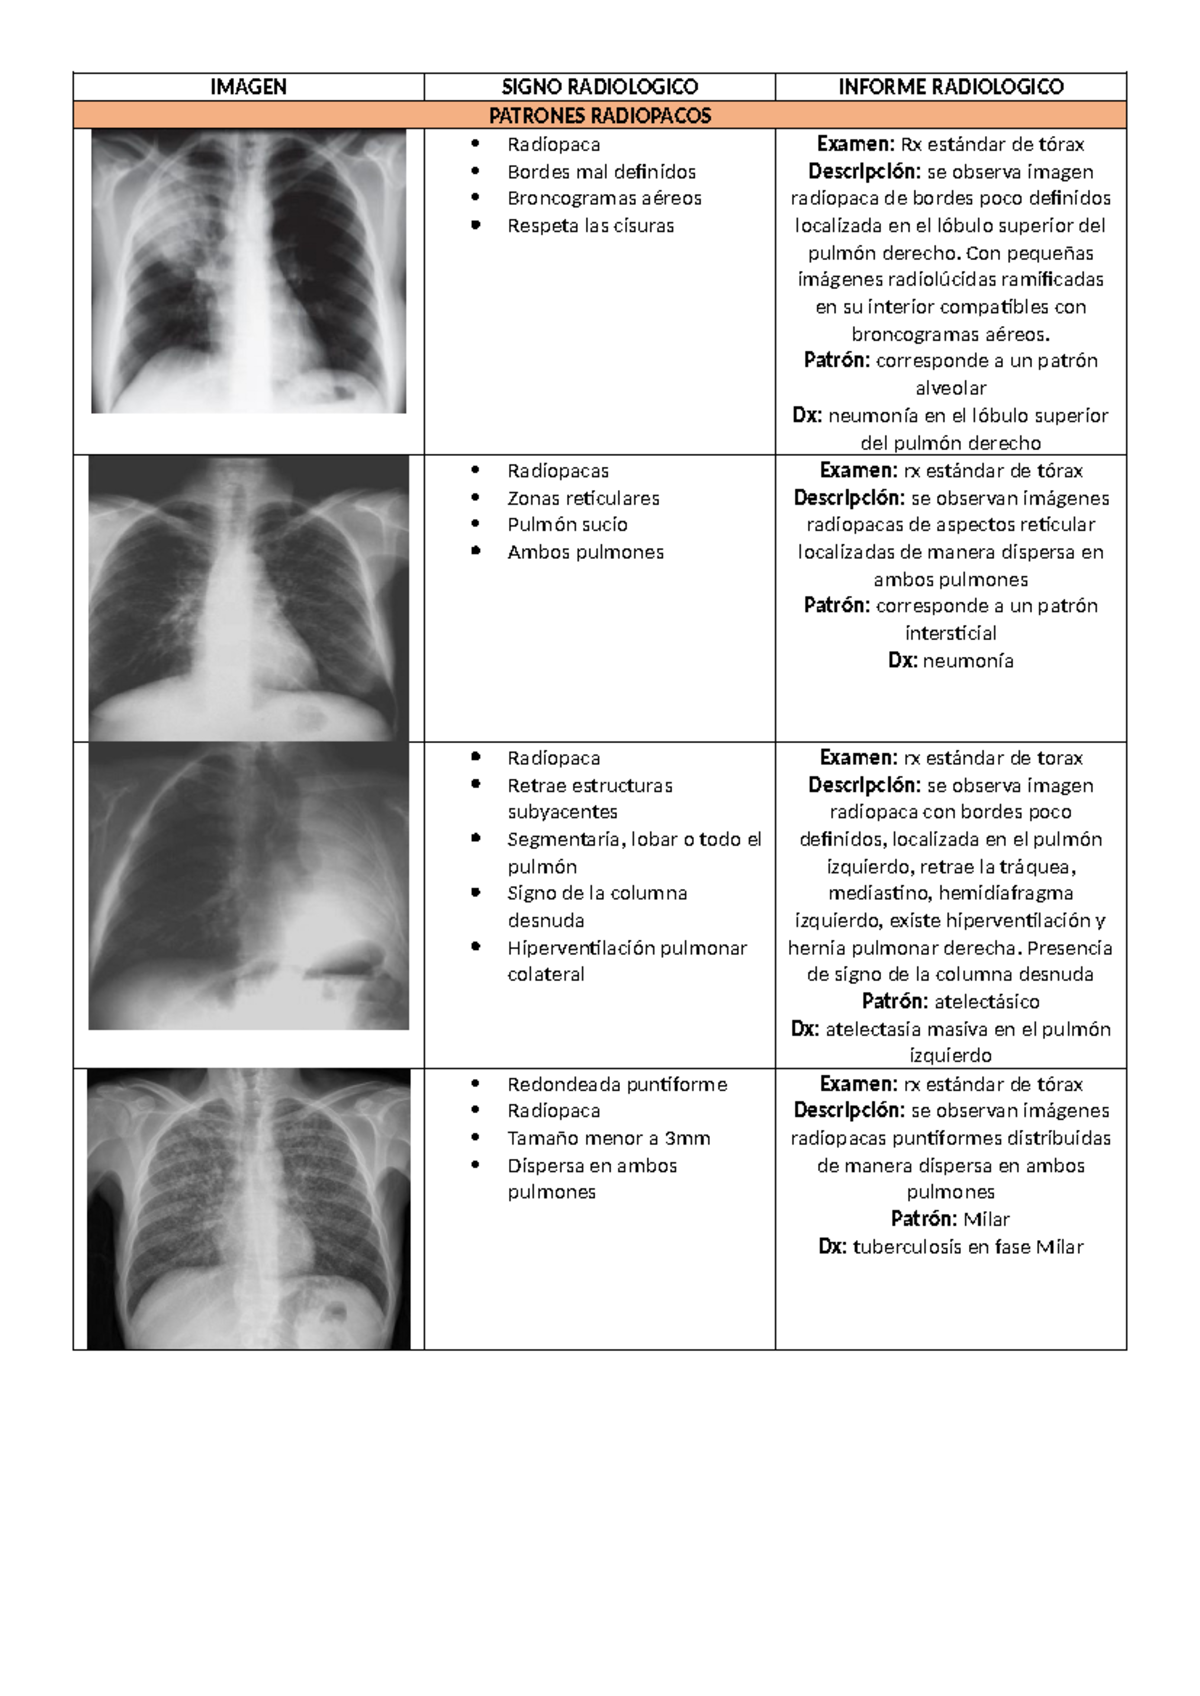

IMAGEN SIGNO RADIOLOGICO INFORME RADIOLOGICO PATRONES RADIOPACOS  Radiopaca  Bordes mal definidos  Broncogramas aéreos  Respeta las cisuras Examen: Rx...